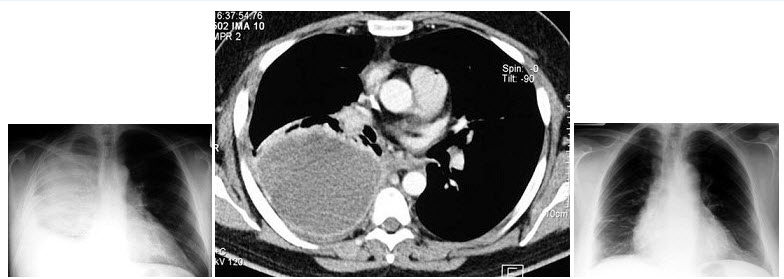

28、单项选择题

女,52岁,头痛、恶心、步态不稳,胸部和颅脑增强CT检查如图,最可能的诊断为()